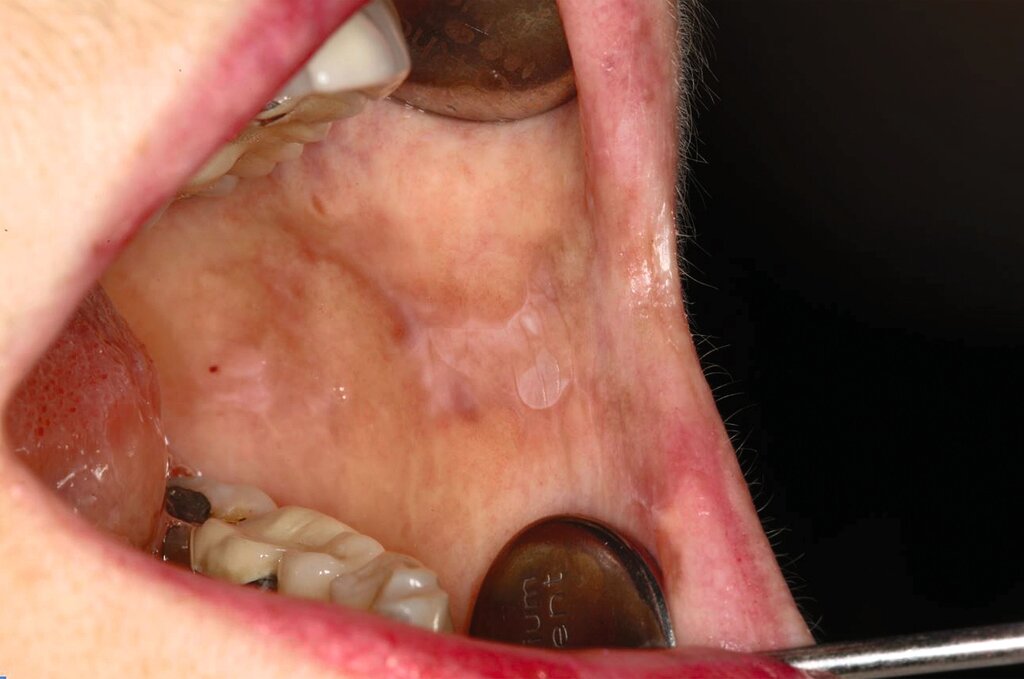

Trotz sorgfältiger Probebiopsie kann es in komplexen Fällen zu einer Diskrepanz zwischen dem histopathologischen Ergebnis und dem klinischen Befund kommen. Die S2k-Leitlinie „Diagnostik und Management von Vorläuferläsionen des oralen Plattenepithelkarzinoms in der Zahn-, Mund- und Kieferheilkunde“ empfiehlt in solchen Fällen eine erneute histologische Überprüfung oder eine Überweisung in eine entsprechende Fachklinik [van der Waal, 2009] Die Abbildungen 7 bis 9 zeigen die Entwicklung einer Leukoplakie der Zunge (Abbildung 7), ihre Transformation in ein orales Plattenepithelkarzinom (Abbildung 8) sowie den klinischen Situs nach chirurgischer Therapie (Abbildung 9).